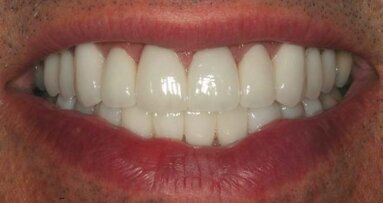

Fig. 8: Post-op full smile.

The patient returned the following day. Her functional oc­clusion was evaluated, and her teeth were inspected for any re­sidual cement. Postoperative radiographs were taken to con­firm positive seating of the margins and the absence of any residual interproximal cement. Maxillary and mandibular alginate im­pressions were taken along with a polyvinylsiloxane bite reg­istration for fabrication of a maxillary full-arch bite guard for night-time wear.6 Postoperative home care instructions were given, and the patient was scheduled for a follow-up appoint­ment for additional photographic documentation, a final check for function and aesthetic evaluation, and delivery of the bite guard (Figs. 8 & 9).6